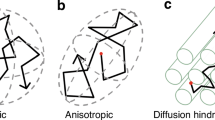

To date, however, there have been very limited studies on the segmentation of SLF sub-bundles in human foetuses and neonates. Previous histological studies indicate that the outgrowth and ingrowth of long corticocortical pathways finish in the cortical plate during the late preterm phase (33–35 weeks post-conception) (Kostovic 2006). Another recent study found that at 32 to 35 gestational weeks (GW), the SLF can be divided into a deep, direct component (arcuate fasciculus, AF), and a more superficial indirect component using the WM dissection technique (Horgos et al. 2020). Nevertheless, the SLF is not prominently visible with diffusion tensor imaging (DTI) tractography even at birth (Zhang et al. 2007), and most neurodevelopmental studies have considered the entire SLF as a single entity (Ouyang et al. 2015, 2019; Yu et al. 2020). Obviously, SLF tracts estimated by DTI at a very early age do not reflect actual anatomical connectivity. There are some complicated factors contributing to this. First, the quality of dMRI images of foetuses and neonates is limited by the scanning time, magnetic field intensity and other conditions (Dubois et al. 2021). On the other hand, the SLF is one of the slowest maturing WM tracts with lower myelination, and many fibres intersect with it in its running areas (Zhang et al. 2007; Dubois et al. 2009; Geng et al. 2012). Previous studies have shown that the DTI technique may obtain more false negatives at points of crossing, kissing and twisting fibres, which can affect the ability to reconstruct streamlines of the SLF; thus, the full extent of the SLF was not identified (Makris et al. 2005; Kamali et al. 2014; Hecht et al. 2015). All these factors could lead to a reduction in DTI tracking accuracy and loss of structural properties of SLF branches. Constrained spherical deconvolution (CSD) can overcome the crossing fibre limitations inherent in the diffusion tensor model and minimize the bias by tracking through regions with multiple fibre orientations (Thiebaut De Schotten et al. 2011; Jeurissen et al. 2014; Wang et al. 2016; Nakajima et al. 2020; Amemiya et al. 2021), obtaining more reliable tractography results of the neonatal SLF branches.